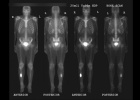

21 year old male with increasing leg pain and enlarging mass for three years